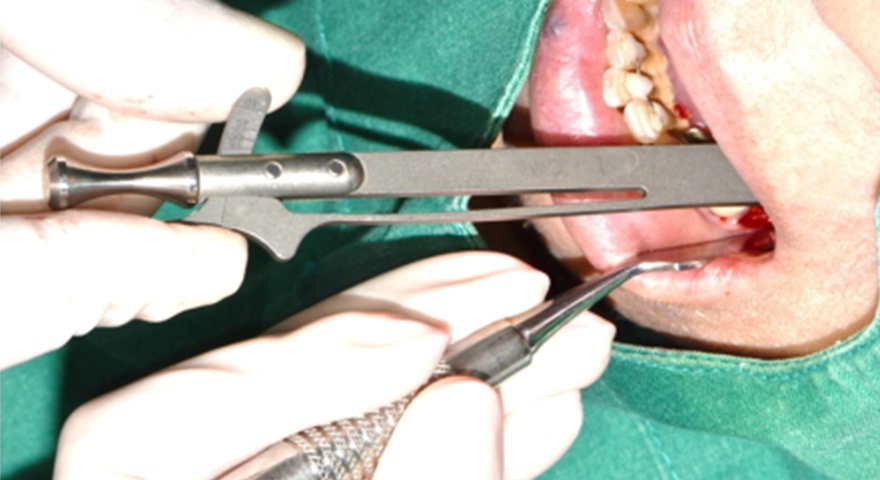

Після проведення стандартної імплантації в ділянках з оголеною різьбою було застосовано техніку DUK: на імплантат наносили спочатку пастоподібний матеріал, далі — гранули, після чого укладали мембрану та закривали клапті швами без натягу. Всі пацієнти отримували антибіотики (амоксицилін) та знеболення (ібупрофен), а через шість місяців — проходили контроль та біопсію ділянки.

Рис. 2. (A) Пацієнт із виявленою необмеженою (non-contained) втратою кісткової тканини та оголенням імплантату з букального боку на момент встановлення імплантату. (B) Нанесення основного шару пастоподібного кісткового матеріалу перед внесенням гранульованого кісткового трансплантата. (C) Укладання колагенової мембрани з покриттям зони трансплантації — від букального до піднебінного боку — та фіксували за допомогою внутрішніх періостальних швів. (D) Через шість місяців після аугментації — візуалізується регенерація кістки з букального боку в ділянці раніше оголеної різьби імплантату.